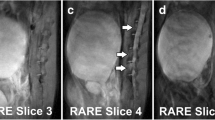

Parametric maps of the patient with metastatic ovarian cancer. a A parametric map of tumor pHe determined with Bloch fitting is overlaid on the anatomical image. b A parametric map of tumor concentration determined with Bloch fitting is overlaid on the anatomical image. c A parametric map of tumor pHe determined with Lorentzian fitting is overlaid on the anatomical image. d A gradient echo MR image showed the location of the tumor and kidney. e Arterial, f venous, and g delayed contrast enhanced gradient echo MR images showed different levels of agent uptake in each tumor.